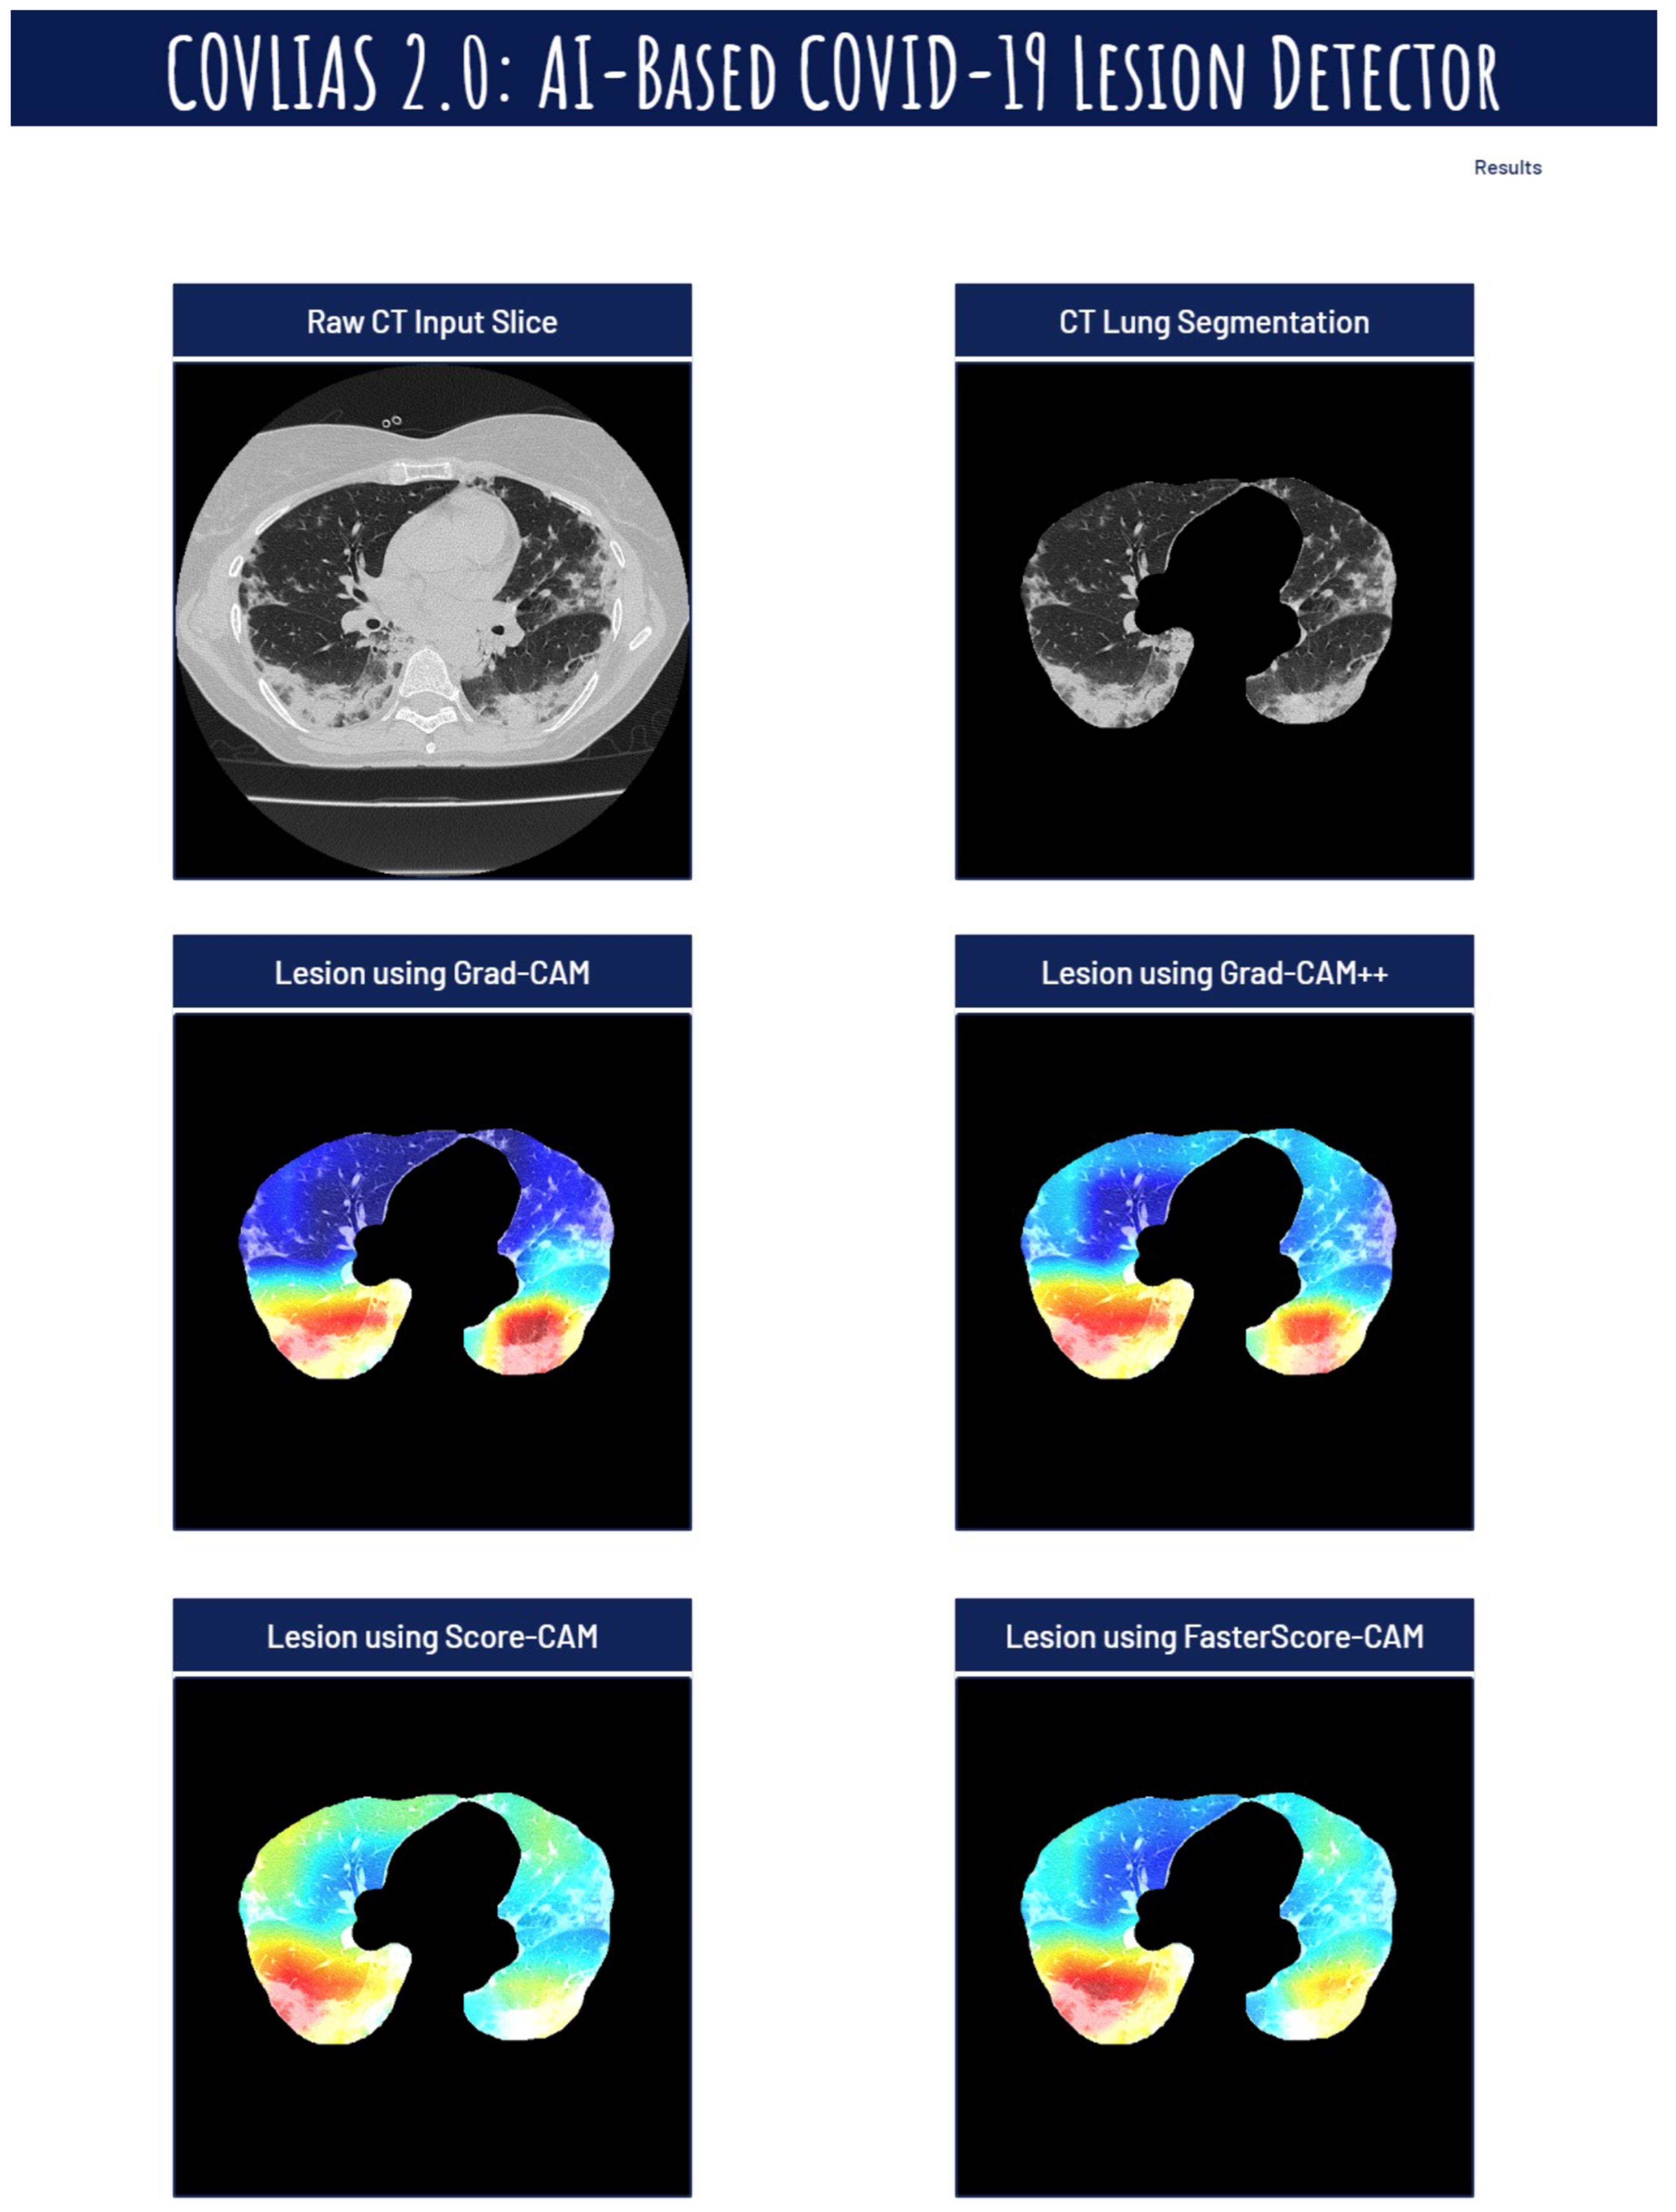

Visual Results Representing Lesion Using the Four CAM Techniques

4.4. A Special Note on Four CAM Models